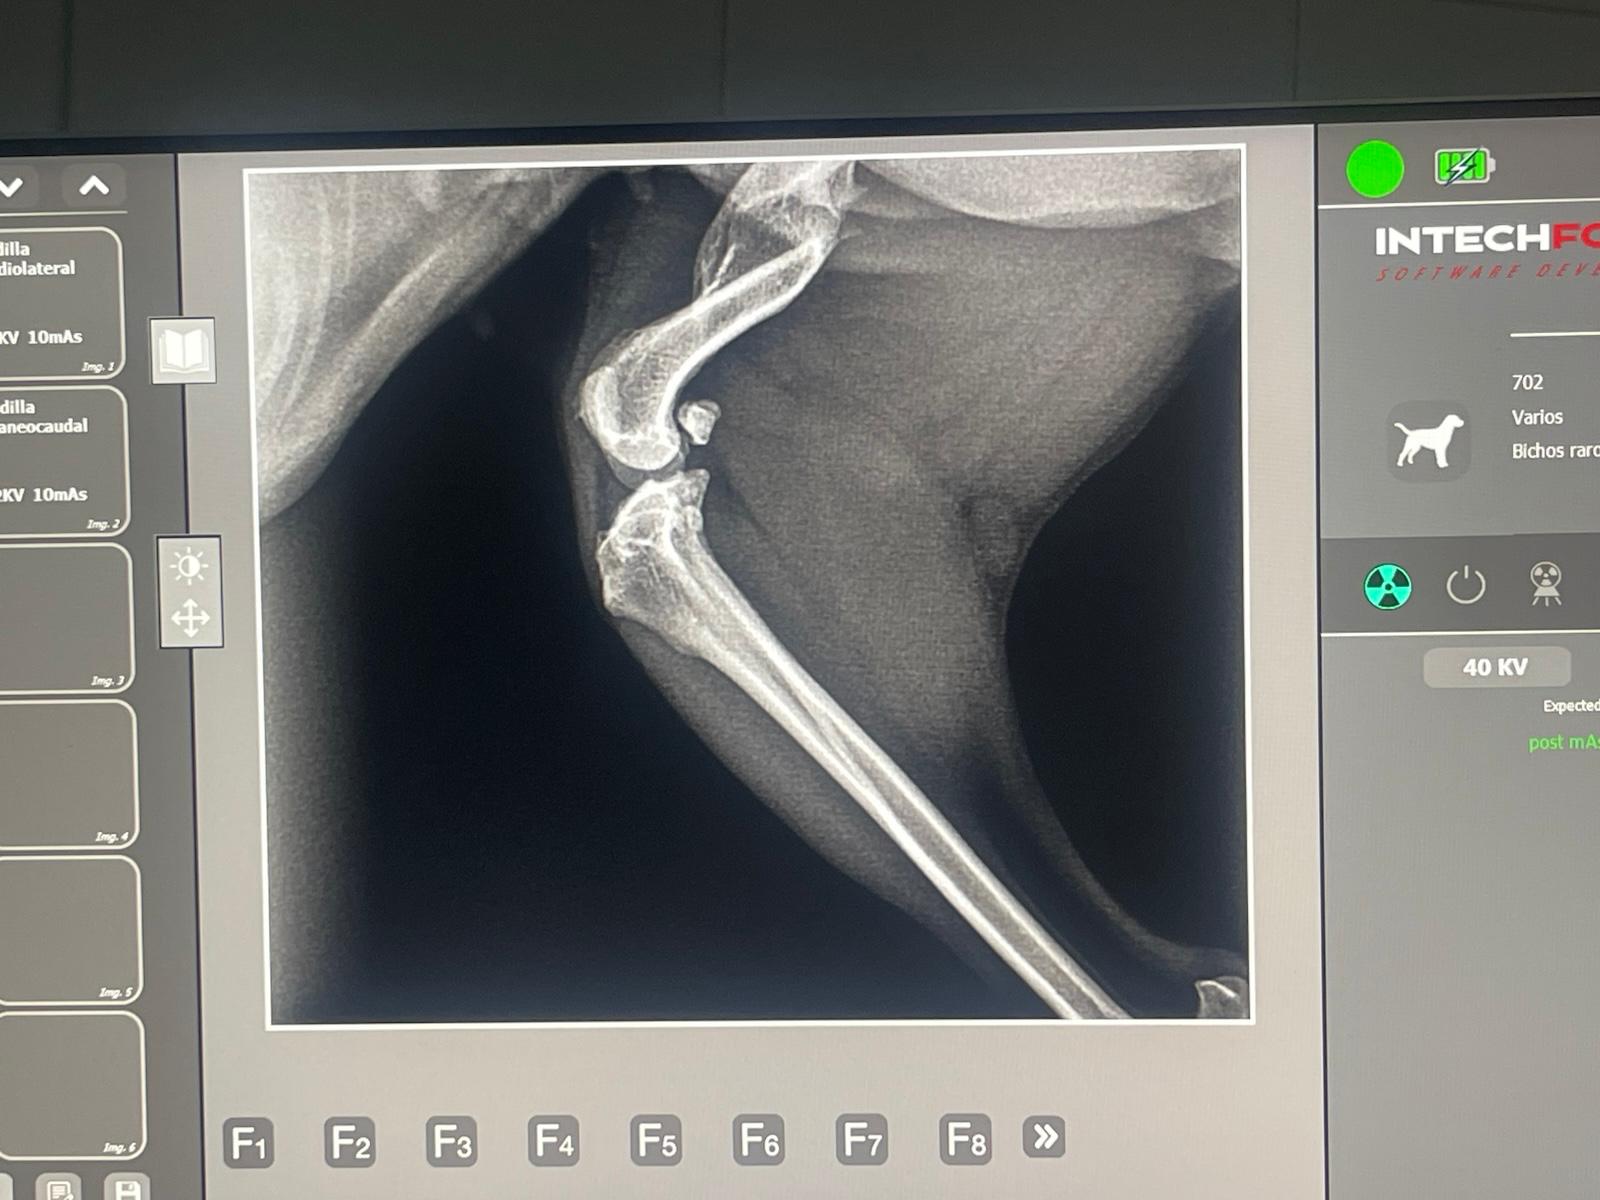

- SKADI: mini pinscher de 2 años y apenas 4 kilos. Ha llegado de una perrera del Sur, donde acabó tras ser encontrada abandonada en pleno temporal de lluvias torrenciales y con una fractura severa en la pata. La pobre está aterrada y no para de temblar de miedo, pero aquí le enseñaremos lo que es el amor y el cariño.